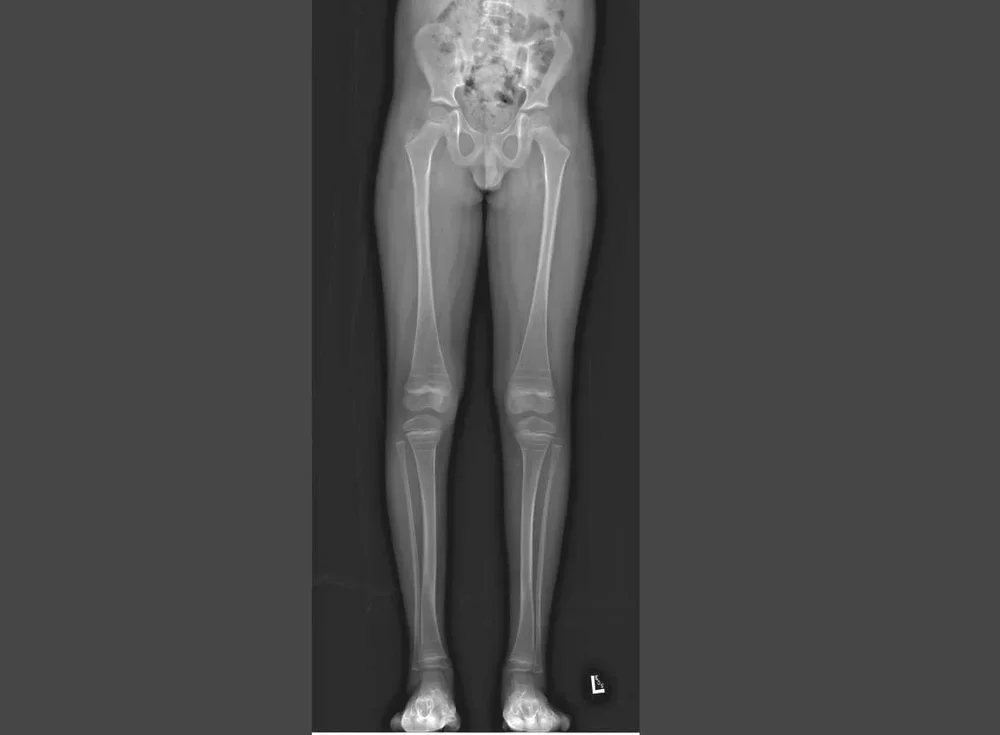

Observational Study of Children with Limb Deformities/Limb Deformity Database

Aim: To prospectively record outcomes of various treatment procedures for children with limb deformities. This study will enable us to compare time in corrective frames, number of surgeries, and complications and help us determine any changes required in our ongoing clinical care.

International Limb Differences Registry (ILDR)

Aim: To capture the full spectrum of diagnoses leading to limb differences through a prospective, global registry.